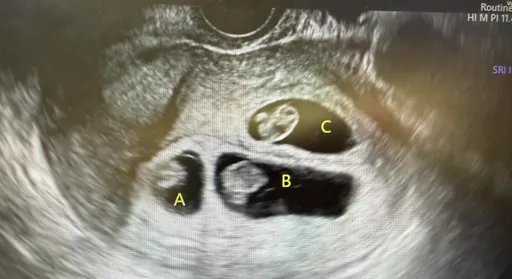

排卵药吃5天就吃出「三胞胎」!医师曝真实案例